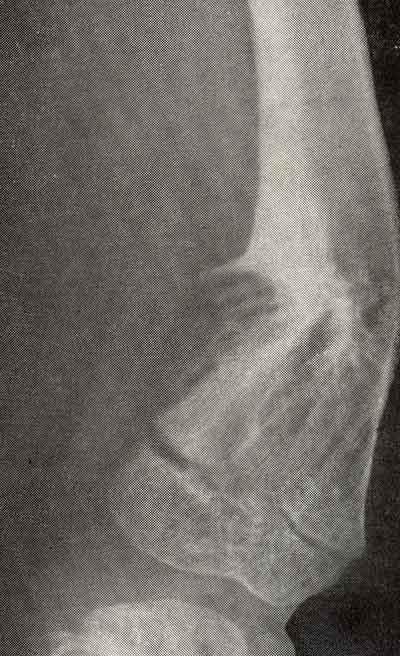

Симптом костного козырька при дисхондроплазии

В мелких трубчатых костях кистей и стоп хрящевые очаги занимают весь диафиз, вызывая его веретенообразное вздутие. Нередко эти очаги множественные. При поднадкостничном расположении истончение кортикального слоя или полное его отсутствие на отдельных участках кости приводит к образованию козырька в результате нависания над хрящевым очагом края кортикального слоя.

Симптом козырька является характерным рентгенологическим признаком дисхондроплазии у детей (у взрослых в связи с оссификацией очагов он не встречается). Структура очагов разрежения обычно неоднородна, в очагах видны вкрапления костной ткани в виде множественных точечных образований с булавочную головку. Иногда вкрапления обильны, что говорит об активно происходящей оссификации эмбрионального хряща. Французские авторы такой процесс оссификации в плоских костях сравнивают с картиной «пылающего куста».